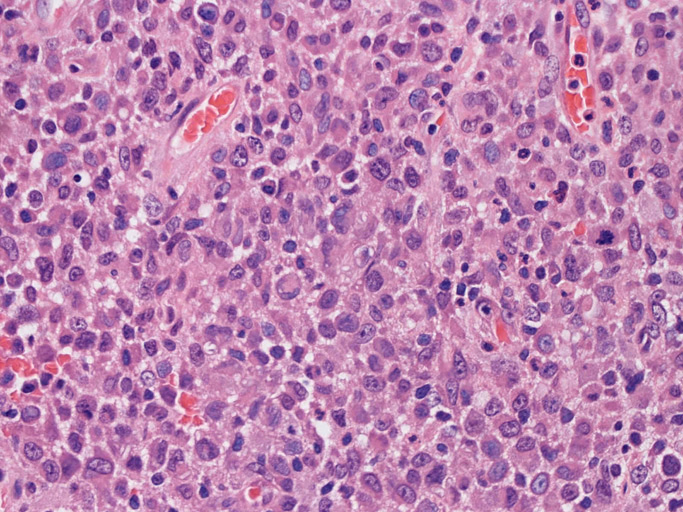

大型細胞の増殖よりなる腫瘍。縦溝,しわ,切れ込みのある核をもった大型細胞も出現する。クロマチンは顆粒状で核小体も明瞭である。核分裂は >50/10hpfと多い。eosinophilsは少ない。壊死が多発することがある。未分化ないし低分化な細胞像, 組織所見のため鑑別診断は多岐にわたり、的確な免疫染色を行う必要がある。

皮膚に異型細胞の浸潤がみられる。異型細胞は表皮内に浸潤するほか、表皮真皮境界部, 真皮, 皮下脂肪組織にもびまん, 結節様の浸潤所見を示す。血管周囲に浸潤、集蔟する所見も多く見られる。 増殖浸潤細胞の核には類円形や腎臓形, またはへこみ, 切れ込み, 溝などを有する多型な核が認められる。クロマチンは粗でvesicularな核が多い。核小体の明らかな核もある。好エオジン性の核内封入体様構造も少数に見られた。mitosisは容易に認められる。hyperchromaticな多型核, bizzarreな細胞が高頻度に認められ異型度は高いと考えられる。細胞質は境界不明瞭, 淡明または泡沫様の 好エオジン性胞体である。

免疫染色 浸潤細胞はCD1a+, S100+, Langerin+, HLA-DR+, CD4+, CD45+, CD68+. MIB-1 index:24.4%